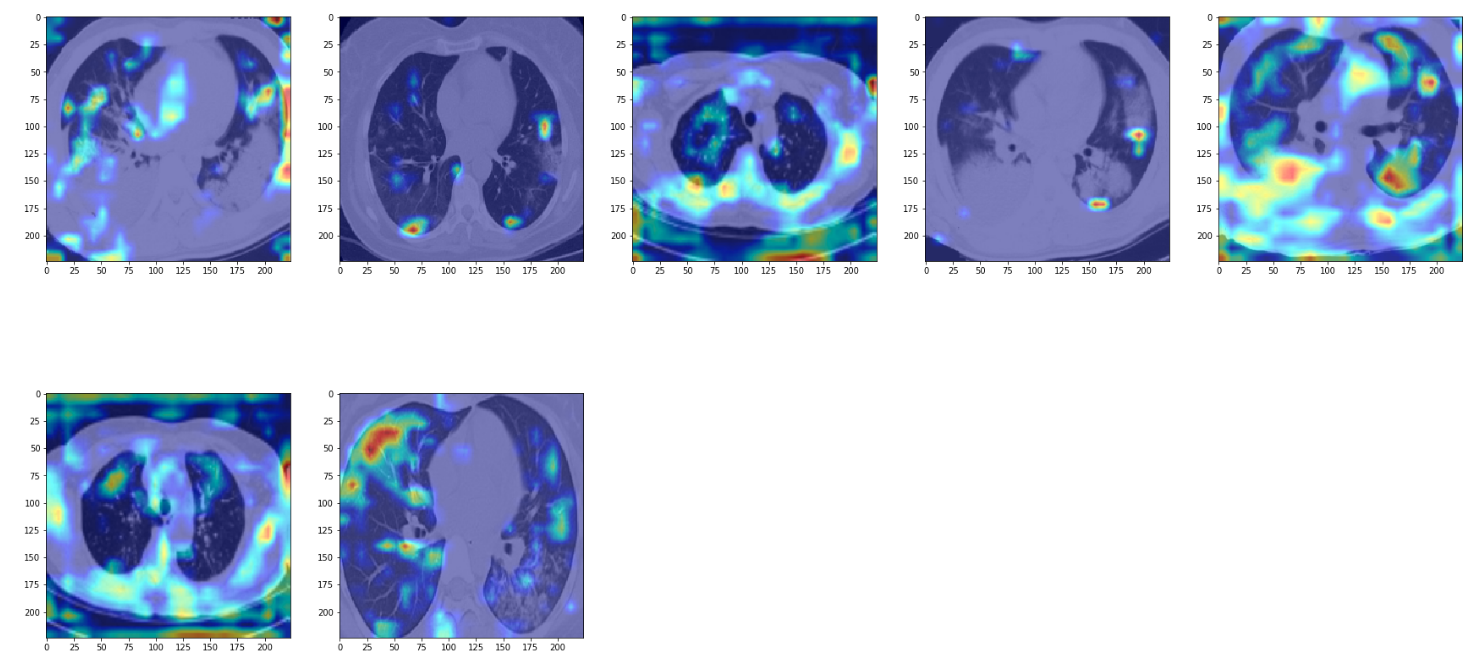

Let us now use the grad cam functionality to visualize a few examples from True positives, True negatives, False positives and False negatives.

We see the model is able to focus on the ground-glass deformities that are characteristic of CT scans of COVID-infected patients. However, we also see that at times the network focuses on the boundary of the lung (in gray color) to make the decision. I am no radiologist to say whether we should be looking at the boundary to make the decision, but if not, then this is something that merits further inspection.

False Positives

In these examples, we see that the network focuses again on opacities but it isn't quite efficient enough to identify opacities corresponding to non-COVID pneumonia from COVID pneumonia.

True Negatives

In true negatives, the network seems to be focusing more on the lung boundary rather than the opacities in the lung. The opacities it sees are not very dense, or ground-glass like. Again, since I'm no radiologist I may be totally off track, but it seems as if the model depends on scarcity of opacities to make the negative prediction.

False Negatives

At last, in false negatives, the network is able to pick up on opacities but classifies them as negative. It seems as if the network has some threshold for opacities. In this case, it seems as if the network is thinking of them of as non-COVID pneumonia. In particular, for the images in row 2, col 2 and row 1, col 3, the network has hardly anything to work with.

Another artifact we see is the network focusing on edges of the image, which might be due to overfitting.